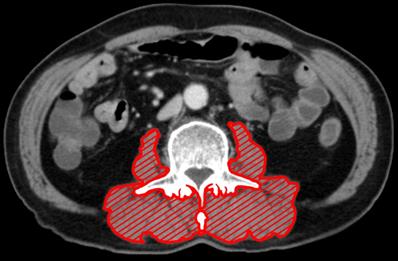

Computed tomography images taken within 30 days before surgical resection were analyzed. After identification of the L3 landmark, corresponding single axial image was extracted and saved as a DICOM image file [24]. SliceOmatic software (ver. 5.0) was used to measure the patient's body composition. Hounsfield unit (HU) threshold (-29 to +150) was used to identify and quantify PMA and PMMA. For measurement of the PMA, the erector spinae, multifidus, psoas, and quadratus lumborum were encompassed (Fig. 1). The PMI was calculated by dividing PMA by the square of the patient's height in meters. Finally, PMMA at the level of L3 was calculated; Region of interest was characterized as all pixels within muscle HU range (-29 to +150 HU). All the measurements were performed by an experienced nurse, and the tagged image file was reconfirmed by an experienced physician before entering it in the database. All measurements were performed under the supervision of a musculoskeletal radiologist. Before statistical analysis, muscle area and attenuation were categorized with sex-specific cutoff points.

Figure 1

The cross-sectional area at L3 of paraspinal muscle (including erector spinae, multifidus, psoas, and quadratus lumborum). Paraspinal muscle is highlighted in red.